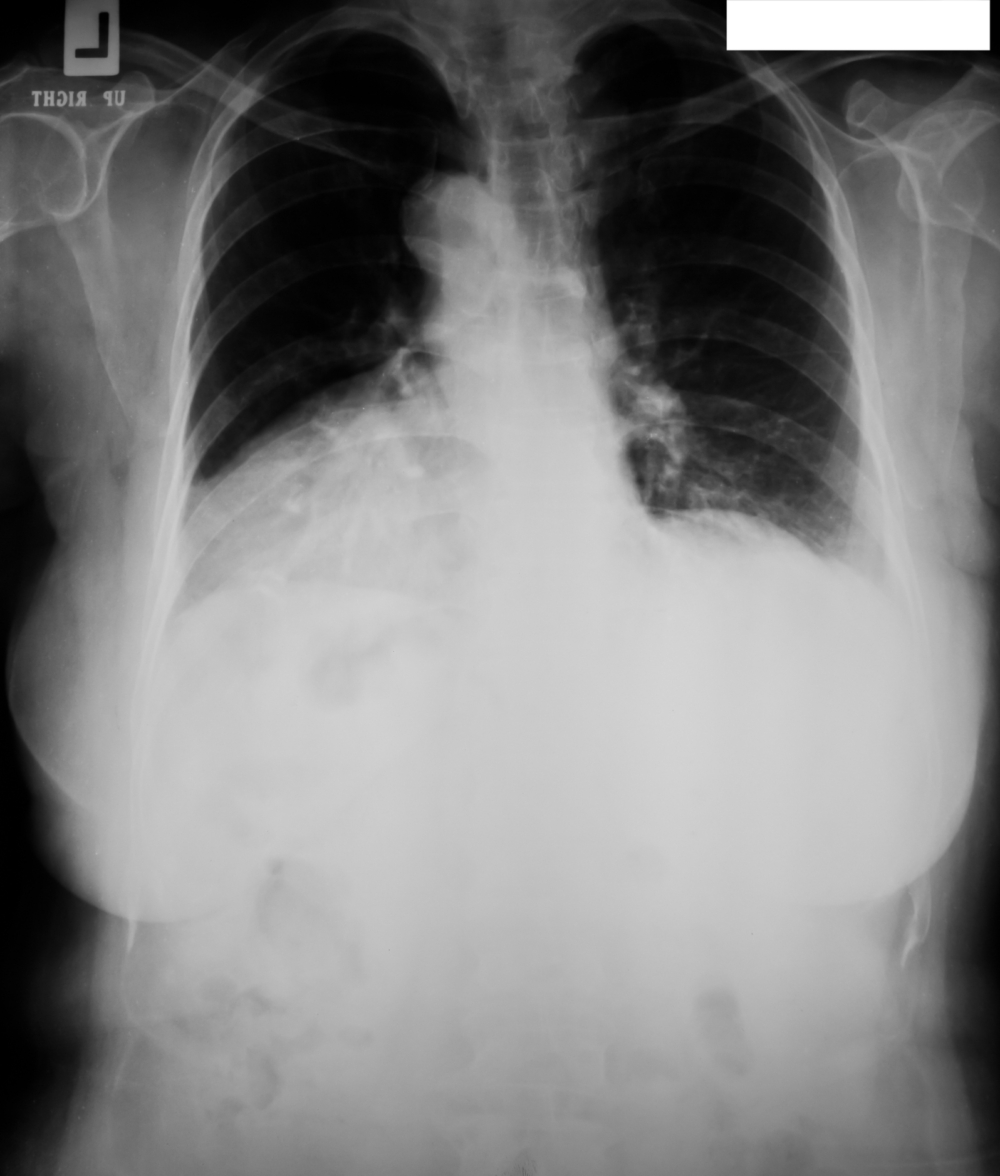

絕少情況出現「白肺」

雖然現時患者以兒童為主,其實任何年齡人士,都有機會患上肺炎支原體感染。內地有傳患者變成「白肺」,陳醫生說:「就算小朋友感染了,很少會演變成『白肺』,白肺是籠統的稱謂,意指嚴重的肺炎,照X光片時肺部呈現白色,但大部份患者都不會去到這個程度,所以家長不用擔心。」